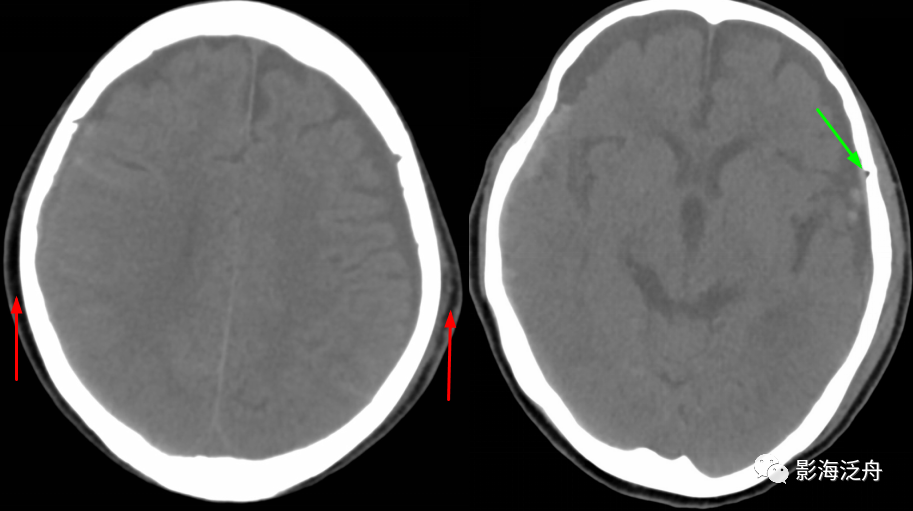

夜班不求人——颅骨骨折(上)_病例

图片尺寸909x507